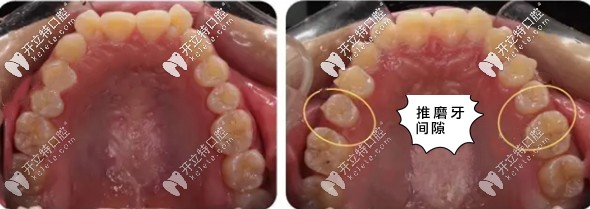

<真人案例展示>? ? ?↓隱適美磨牙后推的矯正案例圖

在正畸中,所謂的推磨牙向后,就是將口內(nèi)的磨牙依次往后移動,來給前牙區(qū)的牙齒獲得內(nèi)收和排列的空間。

把磨牙往后推,是隱適美矯正器的強(qiáng)項(xiàng),通常每一側(cè)可以推出4-5個(gè)毫米的間隙,有醫(yī)生推出了十毫米(這點(diǎn)因人而異,根據(jù)個(gè)人軟組織情況,避免過量遠(yuǎn)移引起冠周炎)。

后推磨牙對于安氏二類的擁擠牙、齙牙,配合片切,較大程度的避免了拔牙,但是它的特點(diǎn)就是前期變化慢,只有磨牙牙縫的變化。

因?yàn)槟パ烙?~4根的牙根,還彎曲、分叉,扎根牢固,移動相對困難,而且是兩到三顆后磨牙都要先后移動,因此,這個(gè)階段的矯正是比較漫長的。